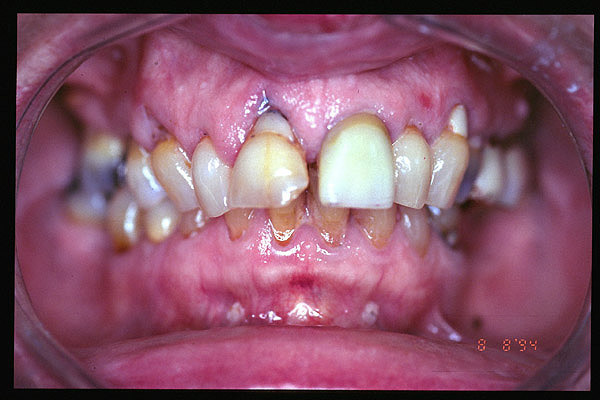

CM Enfermedad periodontal avanzada